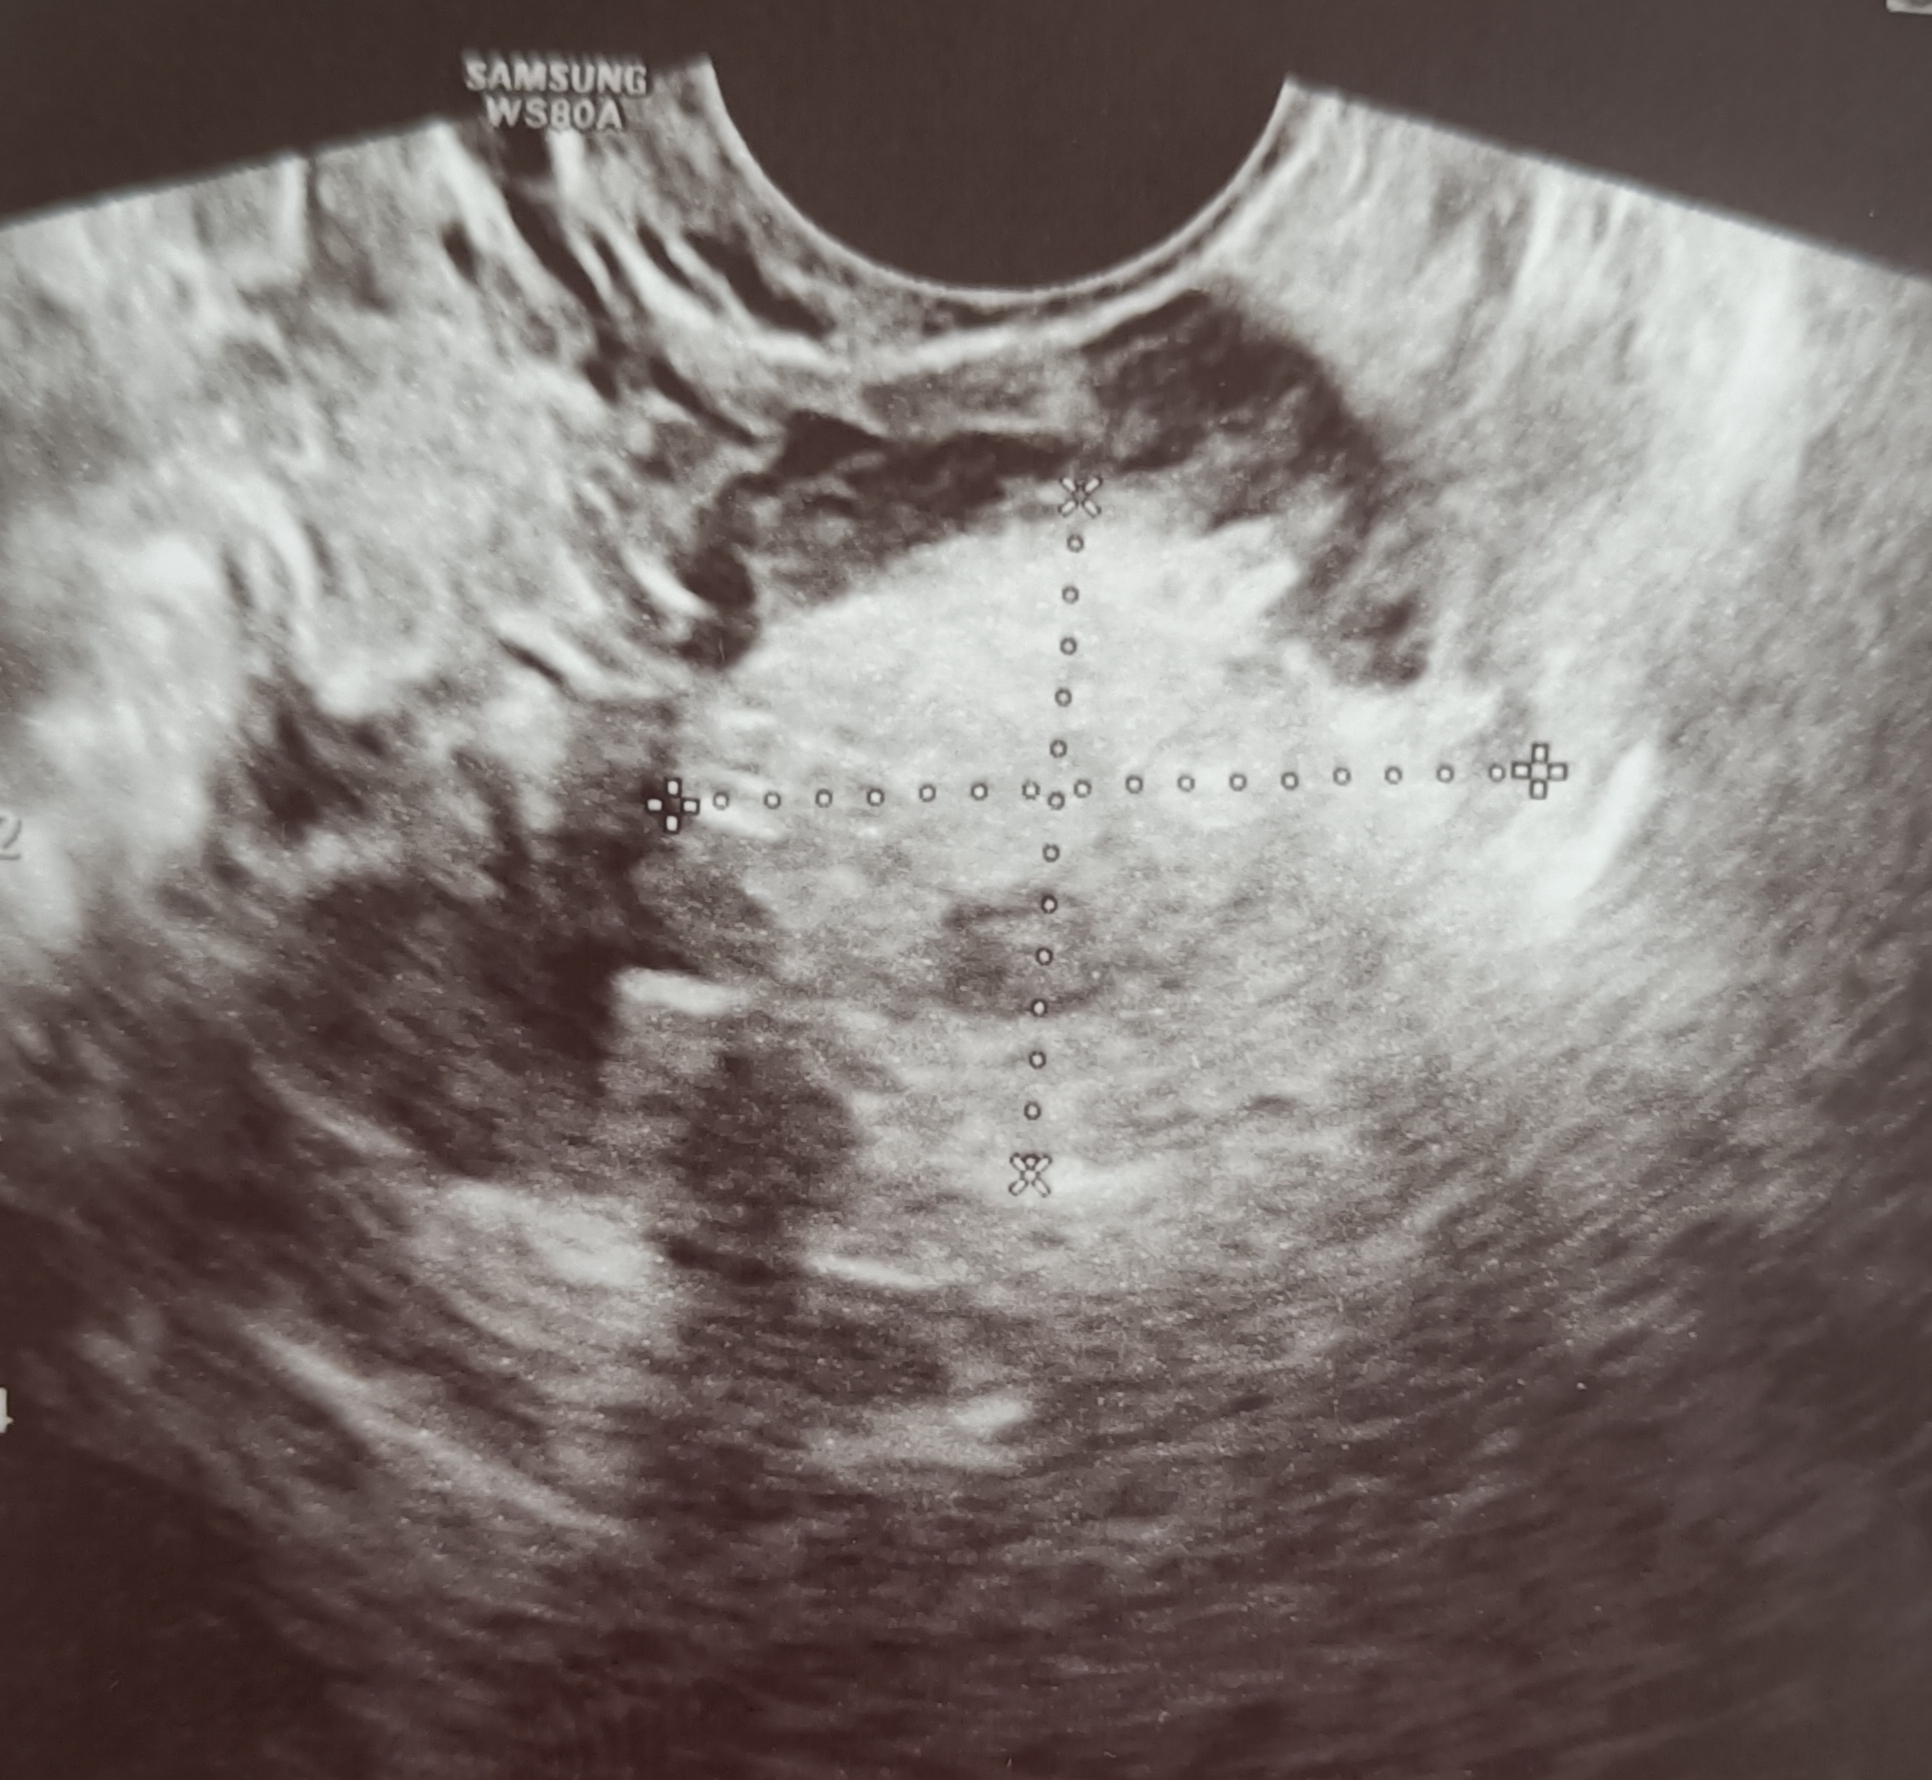

Amandeep Kaur, 35 years old female. Had a previous history of left salpingectomy done for ectopic tubal pregnancy in the left tube. Ultrasound now showed a dermoid cyst in the right ovary. The cyst was removed laparoscopically while preserving the ovary. The cyst showed a tuft of hair, and the biopsy report showed some skin elements too (ectodermal element).